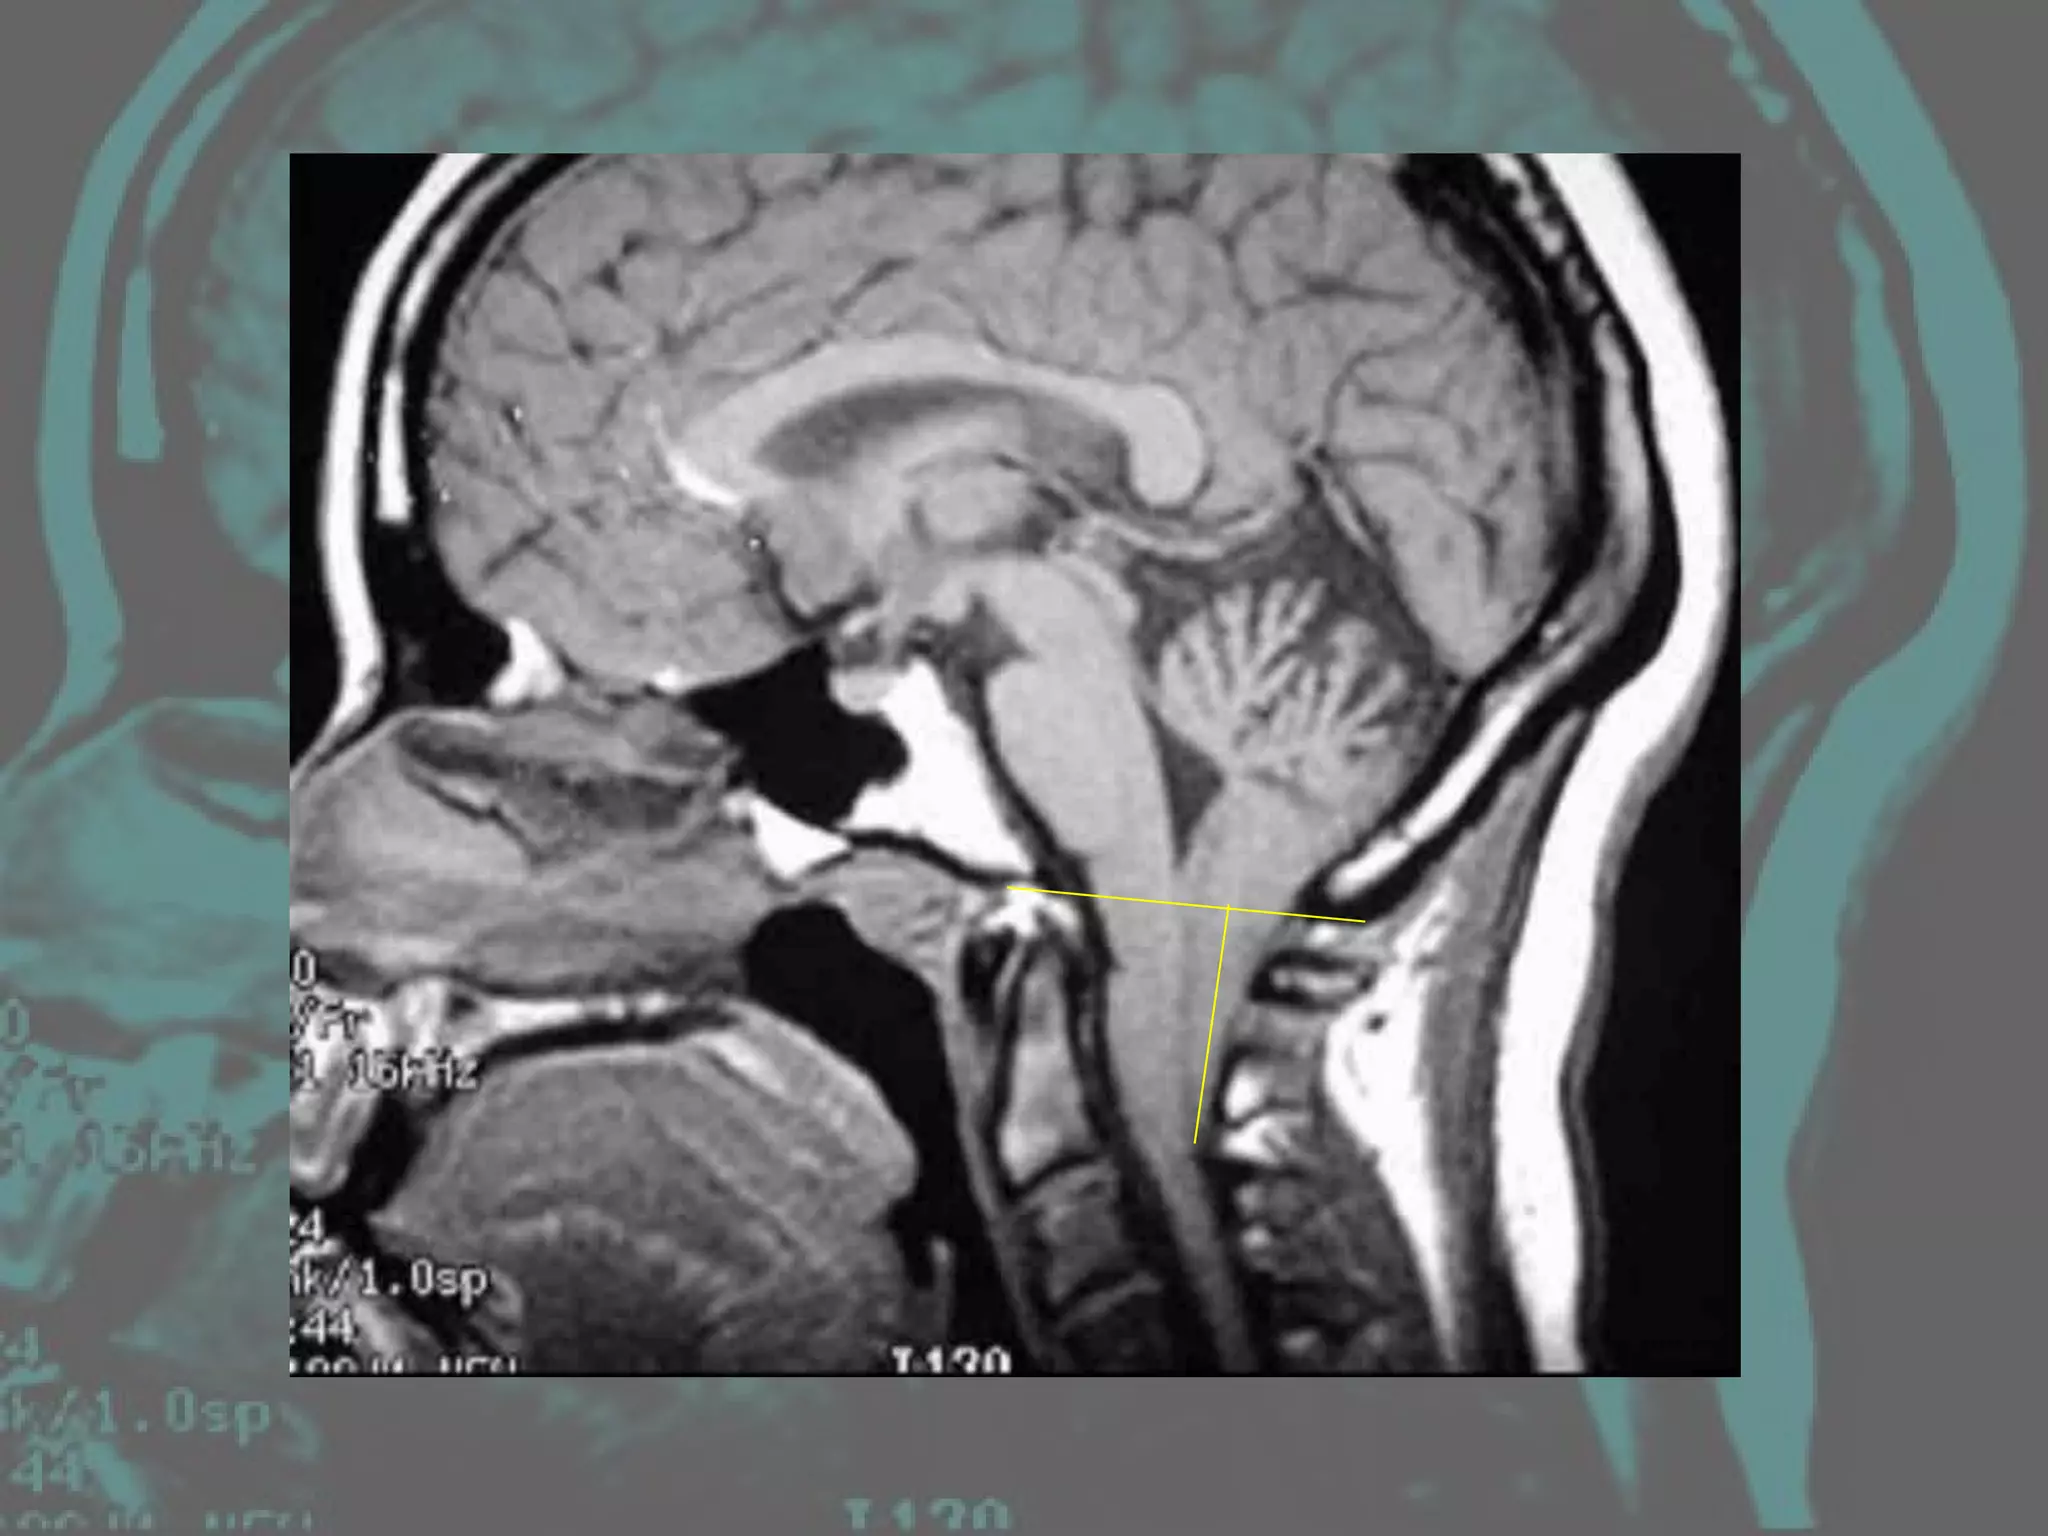

Diagnosis High resolution MRI Degree of tonsillar descent in ACM Significant mass lesions at the craniocervical junction in conjunction with syringomyelia Plain SXR of craniocervical junction Computed tomography (CT) scan Myelography with water-soluable contrast

Teo C, Parker EC, Aureli S, et al: The Chiari II Malformation: a surgical series.  Pediatr Neurosurg 27: 223–229, 1997 Magnetic resonance images of the craniocervical junction should be obtained in all three planes (coronal, sagittal and axial) to evaluate the CSF signal around the medulla within the foramen magnum. If there is no CSF signal around the cord at the level of the foramen magnum, or if a restrictive band of fibrous tissue is apparent, then decompression should be undertaken .